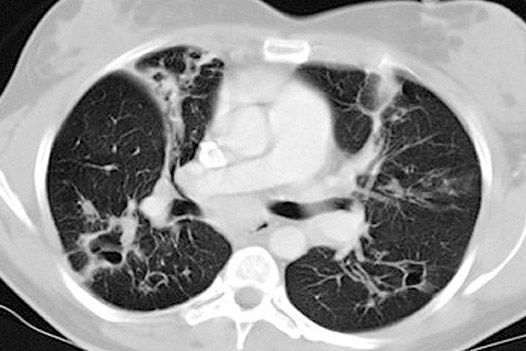

Die Computertomographie ist ein Röntgenverfahren, welches Schnittbilder des menschlichen Körpers erzeugt.

Der Patient liegt auf einer speziellen Untersuchungsliege und wird langsam durch den Detektorring gefahren. Die Röntgenröhre rotiert dabei spiralförmig um einen definierten Körperabschnitt um den Patienten , wobei ein kontinuierlicher Datenblock erzeugt wird mit der Möglichkeit, durch Nachbearbeitung (Rekonstruktionen) Schichtbilder in verschiedenen Ebenen und Schichtdicken, oder ein 3D-Modell der untersuchten Organe (z.B. Knochen, Gefäße) zu erstellen.

• Computertomographie aller Körperregionen